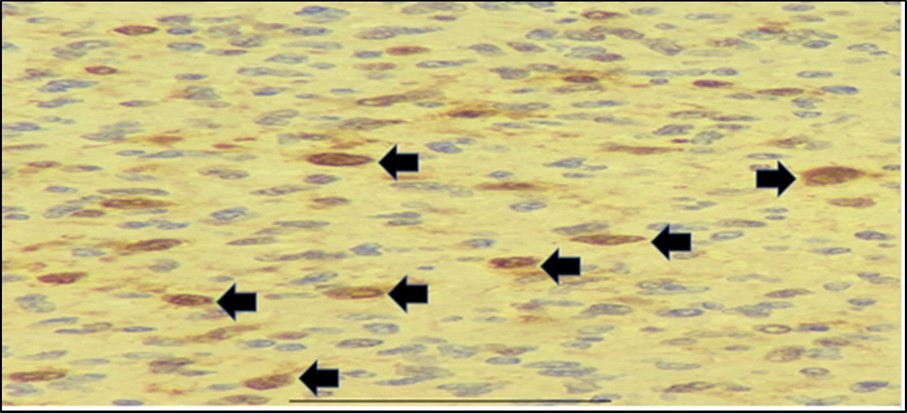

We have a case whose diagnosis needs to be confirmed. The previous biopsy showed histopathology consistent with a neurofibroma, with monomorphic, spindle-shaped, distinct cells, well-spaced, with scant mitosis. Neurofibromas are an autosomal dominant hereditary disease with a varied phenotype that affects the skin and nervous system. Affectation is one out of every 3,500 live births throughout the world. A spontaneous mutation on chromosome 17 is thought to be responsible for around half of the cases7. Figure 3. Comparison between biopsies taken five months apart. The histopathology in the biopsy done in February shows well-spaced uniform cells (black arrows). The biopsy done in July shows cellular congestion with atypical, pleomorphic cells with increased mitotic activity (blue arrows). In the most recent procedure, routine histopathology showed a different picture with higher mitotic figures and cellular congestion. The increased mitotic activity causes cellular production at a greater rate that the resulting cells show atypia and ill-defined borders. Hemorrhage and necrosis are also evident, hinting the tumor growth exceeds its vascular supply. The rapid clinical growth supported the high proliferative nature of the tumor. A diagnosis of Spindle cell sarcoma was made, with low to intermediate grade; however, a final diagnosis cannot be made based on morphology alone. To determine the type of malignancy, a panel of immunohistochemical stains was ordered. Table 1. Immunohistochemical Stain Marker S-100 Tumors of Mesenchymal origin (Sarcomas) SMA Myoepithelial cells Desmin Sarcoma vs Neurofibroma CD34 Epithelioid Sarcoma vs Dermatofibroma CK Tumors of Epithelial origin (Carcinomas) EMA Adenocarcinoma Three screening stains were ordered to identify the origin of the malignancy. S- 100 is a screening stain that becomes positive when exposed to mesenchymal cells. CK screens for malignancies of epithelial origin, while CD34 screens for hematopoietic involvement. Smooth Muscle Actin is a stain used to determine the presence of myoepithelial cells. This was chosen to consider the possibility of pulmonary metastasis. Desmin is a stain chosen due to its ability to differentiate rhabdomyosarcomas from other mesenchymal malignancies. Finally, EMA is a marker used to confirm carcinomatous lesions8 . Since the gross appearance of the tumor closely resembled muscular tissue, the S-100 stain was done first. The stain clearly showed a positive reaction. There was a note of mitotic activity in up to 7/10 high power fields with associated necrosis. This clinched the diagnosis as a mesenchymal tumor, allowing us to rule out three stains – CD34, CK, and EMA, along with their respective differentials of hematopoietic and epithelial tumors9. The initial positive reaction to S-100 allowed a narrowing of differentials to mesenchymal cell origin tumors. We could consider neurofibromas, schwannomas, malignant peripheral nerve sheath tumors, as well as metastatic myoepithelial cells. To help us differentiate, we take a closer look at SMA next. The sample did not stain to SMA, producing a negative result. This effectively ruled out myoepithelial tumors such as metastatic pleuropulmonary tumors, narrowing our differentials to neuronal tumors and smooth muscle rhabdomyosarcomas10. It was decided that determining desmin content would allow us to further narrow the differentials by differentiating between a rhabdomyosarcoma that would stain positively for desmin, and neuronal tumors such as a neurofibroma will be negative staining11,12 The specimen is composed of pleomorphic spindle cells forming sheets with a marbling pattern. Mitotic activity is present in up to 7/10 high power fields with associated crowding and necrosis. This portion of the lesion shows immunoreactivity for S100, while the remainder of the lesion has focal reactivity. Negative stains include SMA and Desmin. Since a neurofibroma can undergo malignant transformation, these last two lesions are what remain among our differentials. While morphologic histologic findings are more consistent with malignant growth, a closer look at the staining characteristics of S-100 can differentiate between the two lesions. In neurofibrosarcomas or malignant peripheral nerve sheath tumors, S100 staining is patchy and focal, with less than 50% of the specimen showing reactivity to staining. In neurofibromas, the S100 reaction is strong and diffuse, staining nearly the entire specimen13. The morphologic changes, immunohistochemical staining, and character of staining of S100 allows us to clinch the diagnosis of a Malignant Peripheral Nerve Sheath Tumor arising from a recurrent neurofibroma. Figure 4. Immunohistochemistry Staining results. S-100 shows selective staining of the cells of interest (black arrows). SMA and desmin showed negative staining of cells. In two population-based investigations, the lifetime probability of developing MPNST in NF1 patients was estimated to be 8-16 percent. Malignant transformation can begin as early as childhood, although it is most common in life's third to fourth decades. The probability of sarcoma-specific mortality is greatest in high-grade MPNST. Overall survival after five years ranges from 20% to 50%, with unresectable or metastatic cancer having a particularly poor prognosis14. Figure 5, Figure 6

Figure 4.Immunohistochemistry staining results. S-100 shows selective staining of the cells of interest (black arrows).